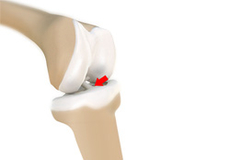

Osteochondritis dissecans is a joint condition in which a piece of cartilage, along with a thin layer of the bone separates from the end of the bone because of inadequate blood supply. The separated fragments are sometimes called “joint mice”. These fragments may be localized or may detach and fall into the joint space, causing pain and joint instability.

Loose Bodies in the Knee

Loose bodies are fragments of detached cartilage or bone inside the knee joint. These fragments may be free floating (unstable) or may be trapped (stable) within the joint. Depending on the severity, you may have one or more loose bodies in your knee joint.